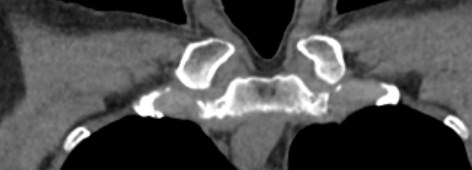

Однако классический рентген не всегда обеспечивает качественную визуализацию ГКС из-за наложения друг на друга изображений костных структур. Компьютерная томография лишена таких недостатков. При проведении КТ излучатель рентгеновских лучей совершает круговые движения вокруг исследуемой области, проводя сканирование в различных плоскостях. В результате получаются детальные снимки высокого качества, а после цифровой обработки – трехмерные модели грудино-ключичных сочленений в мельчайших подробностях.

КТ благодаря быстроте, доступности и высокой информативности часто назначается в экстренных ситуациях, например, при травмах и в случае необходимости проведения оперативного лечения. Поэтому метод особенно востребован в ортопедии и травматологии. На снимках КТ и трехмерных изображениях можно оценить состояние суставных поверхностей грудино-ключичных сочленений, а в случае перелома определить точную локализацию костных отломков.

При необходимости визуализации капсульно-связочного аппарата ГКС и окружающих мягких тканей нативная компьютерная томография дополняется контрастным усилением. Для этого пациенту внутривенно вводится йодсодержащий контрастный препарат, обладающий способностью активно поглощать рентгеновские лучи. Благодаря контрастированию на снимках КТ визуализируются суставные диски, связки, мышцы и окружающие мягкие ткани. Кроме того, контраст в большей степени концентрируется в патологических очагах, что позволяет диагностировать воспалительные изменения и, в первую очередь, опухолевые новообразования как доброкачественного, так и злокачественного характера.